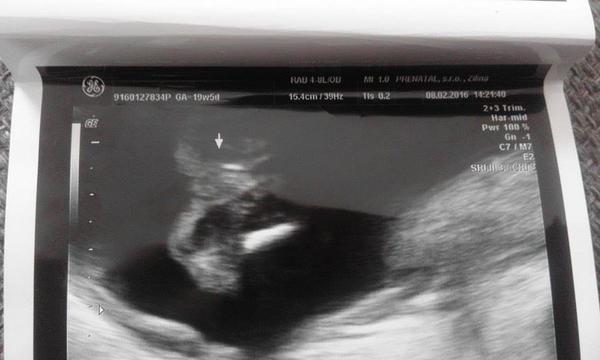

Pomýlil sa doktor pri určení pohlavia na 3D sone v 20 týždni?

no neviem baby ci ste si vsimli, ale za poslednu dobu, dost kratky cas, som sa stretla uz s niekolkymi pripadmi, ked lekari urcili pohlavie na 3D na 100% a nakoniec sa pomylili...

caute baby, ono je to take diskutabilne. poznam rodinku, ktorej celu dobu hovorili, ze to bude chlapec a narodilo sa dievcatko, mojej svagrinke naznacovali dievcatko a je z toho maly Risko 🙂 ale podla mna, ak to potvrdi viac sono, tak je to istejsie🙂

nam v 19 tt povedal lekar, ze to bude chlapec, ze vidno gulky a tie gulky sa nemaju s cim pomylit, ale ties je to vraj na 90%. No vsak uvidime, ci sa to nezmeni, za tyzden idem na dalsie sono to budem v 22tt, tak dufam, ze sa to uz nezmeni, lebo uz som niake vecicky nakupila